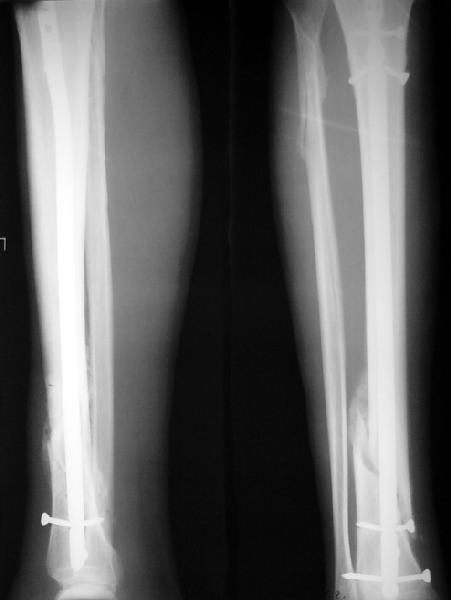

Ok. А также и следующий, в 3 месяца.

Это наглядная демонстрация возможности ранней полной нагрузки при нестабильном по оси повреждении, причем не в самых благоприятных механических условиях - при плохом сопоставлении, со слабым фиксатором.

Сверху - один статический винт, а снизу - три. Что раньше сломается? Конечно, он потом и нижние сломал, и Вы правы, если бы верхний динамичесий винт уже уперся бы в нижний край отверстия, будь гвоздь подлинее, перфорировал бы сустав как пить дать.

Как я уже говорил, мы сделали выводы из этого и других подобных случаев. Очевидно, решений проблемы два - либо уменьшить нагрузку, либо увеличить прочность фиксатора. Первое решение работает не со всеми больными, так что пошли по второму пути - мы больше не используем гвозди с запирающими винтами диаметром 4 мм.